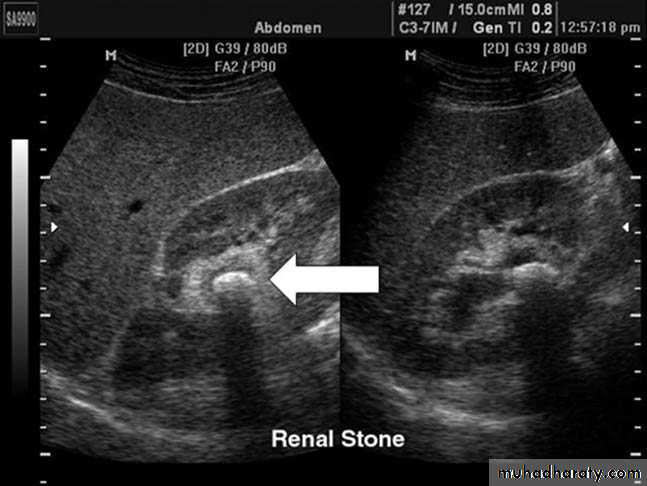

Renal stones